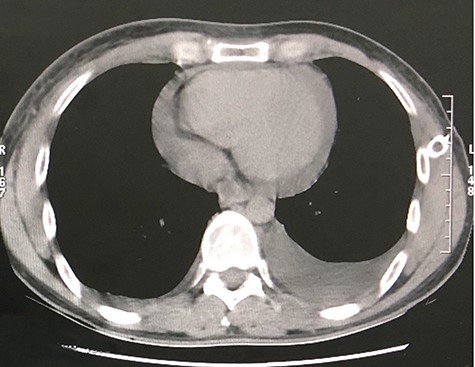

The second case consists of a 47-year-old male from a rural location in Guatemala that presented with malaise, fever, nausea, vomiting and left chest pain, described as oppressive that irradiates toward the neck. The pain got worse while being on supine position. The patient was previously treated with antibiotics and underwent a left thoracostomy due to a chest radiograph that showed a pleural effusion in the lung base (Fig. 3). On chest auscultation and percussion, air entry was reduced and dullness was perceived in the left lung base, respectively. Due to these findings, laboratory tests were ordered. The blood test showed an elevated lactate dehydrogenase at 156 U/L and the pleural fluid analysis showed an elevated lactate dehydrogenase at 1282 U/L, cholesterol level at 66 mg/dl, triglyceride level at 128 mg/dl, presence of Klebsiella pneumoniae and a hematoxylin stain positive for helminth larvae. According to these results, the pleural effusion was classified as an exudate. The high triglyceride level was consistent with a chylous effusion. A chest CT showed left loculated pleural effusion, cardiomegaly, slight pericardial effusion and mediastinal adenomegaly (Fig. 4). The patient presented full recovery after surgical and medical treatment.

CT scan axial view of left pleural effusion, cardiomegaly and pericardial effusion.